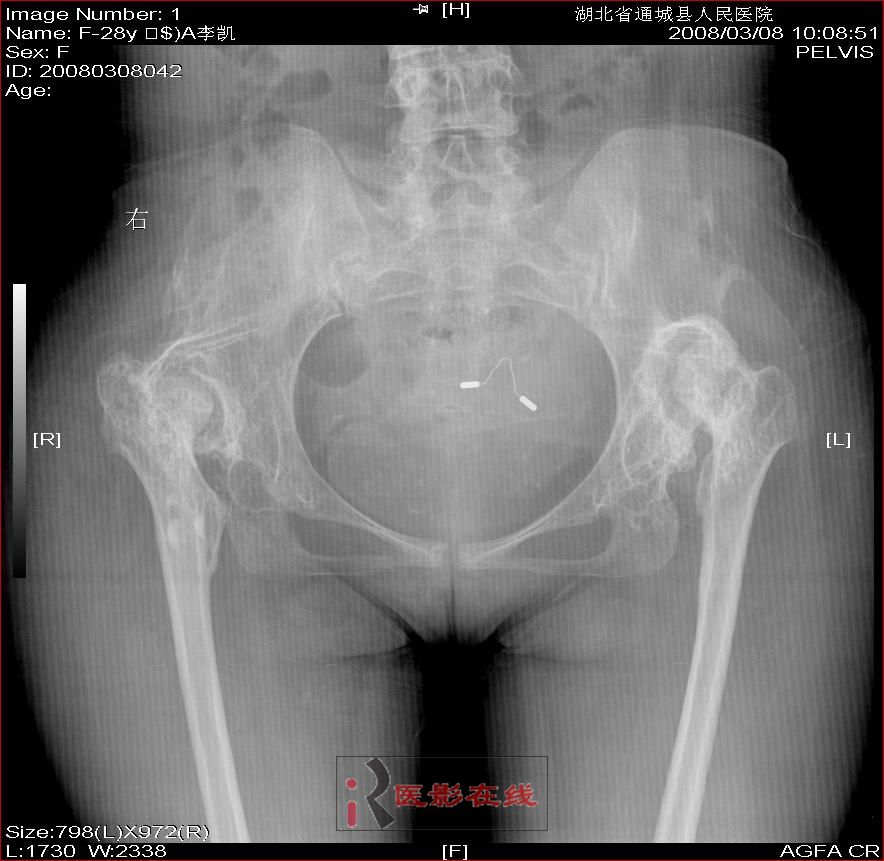

先天性双髋关节脱位自体骨关节再造

女 28岁 先天性髋关节脱位术后复查片(手术日期是2000年,数字化以前平片资料患者外带),现无其它不适,走路仍需双拐

2008年3月8日

1.双髋关节先天性脱位术后改变;2.双髋关节退行性变;3.骨质疏松(骨盆明显)。

双侧髋关节仍为脱位表现,假关节形成,部分已经强直,右股骨头碎裂,股骨干近端增粗。

结合手术史考虑:原地臼盖成形术后,髋关节退变,股骨头无菌性坏死,右股骨近端生长紊乱,骨质疏松。

1.双侧髋关节脱位并假关节形成。